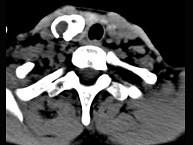

问题 50岁女性患者,体检发现右侧甲状腺有较硬结节,CT扫描如图所示,请选择正确的描述和答案()

选项 A.右侧甲状腺内见稍低密度影,周边围以环形致密钙化影 B.肿块影与周围结构分界清楚 C.考虑为结节性甲状腺肿 D.考虑为甲状腺癌 E.考虑为甲状腺腺瘤钙化

答案 ABE